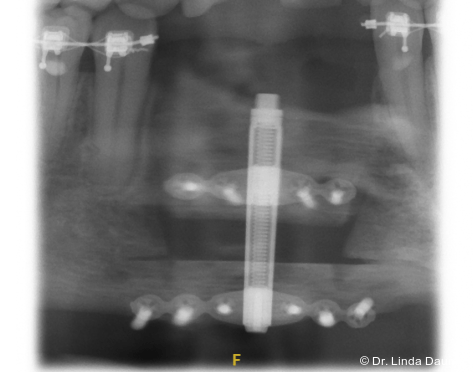

Nach umfassender Aufklärung erfolgte – aufgrund des unzureichenden Knochen- und Weichgewebsangebots für eine unmittelbare Implantation – eine Unterkieferdistraktion zur vertikalen Augmentation des Knochens und zur Vermehrung des Weichgewebes durch eine kontinuierliche Dehnung. In Intubationsnarkose wurde der Knochendefekt dargestellt und das Segment in Regio 32-42 osteotomiert. Das Segment war an der lingualen Schleimhaut gestielt, mobilisiert und gut durchblutet. Anschließend wurde der Distraktor (KLS Martin) angepasst und eingebracht (Abb. 2a–c). Abschließend erfolgten der Wundverschluss und eine postoperative Röntgenkontrolle (Abb. 3).

Nach einer Latenzphase von sieben Tagen begann die Distraktion mit 1 mm pro Tag, aufgeteilt in mehrere Einzelaktivierungen unter engmaschiger Kontrolle. Nach Erreichen der vorgesehenen Endposition begann die Konsolidierungsphase (Abb. 4). Der Distraktor wurde nach acht Monaten entfernt und es erfolgte die Implantation in Regio 32 und 42 mit lokaler Augmentation (Abb. 5a+b). Nach einer weiteren Einheilphase von fünf Monaten wurden die Implantate freigelegt und das Weichgewebe mittels eines freien Schleimhauttransplantats vom Gaumen optimiert. Die prothetische Versorgung konnte anschließend festsitzend mit einer implantatgetragenen Brücke von 32-42 realisiert werden (Abb. 6).